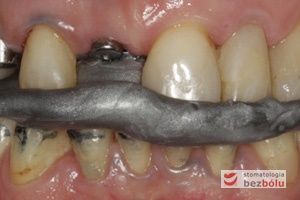

Struktury cerkonu na zębach własnych i łącznikach - strefy boczne odbudowane mostami na zębach własnych  - pojedyncze braki implantami

Struktury cerkonu na zębach własnych i łącznikach – strefy boczne odbudowane mostami na zębach własnych – pojedyncze braki implantami

Struktury cerkonowe od przodu - nieznaczne tatuowanie dziąsła poprzez tytanowe łączniki

Struktury cerkonowe od przodu – nieznaczne tatuowanie dziąsła poprzez tytanowe łączniki